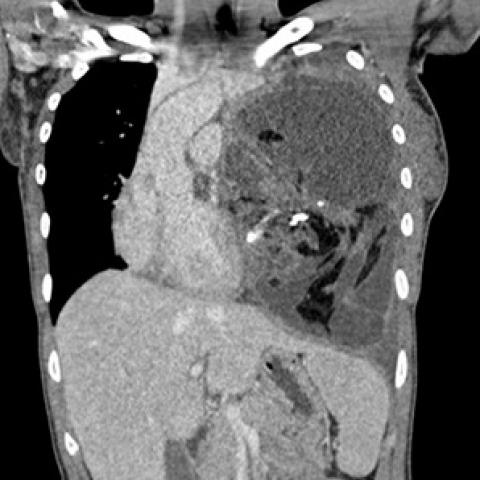

随后进行胸部对比增强CT(计算机断层扫描),结果显示非常大的团块占据左肺大部分,并且左上叶保留。团块由软组织组成,具有肉眼可见的脂肪灶,液性变薄的囊性区和多个钙化灶。CT进一步证实了纵隔移位的程度和左胸腔存在积液。纵隔淋巴结无明显肿大,无骨性病变,无肺扩张。组织学证实有大量成熟的肺内畸胎瘤。

图4冠状面CT显示,左肺内存在大量软组织团块,包括肉眼可见的脂肪、液性变薄的囊性区和多个钙化灶。少量胸腔积液,纵膈移位。